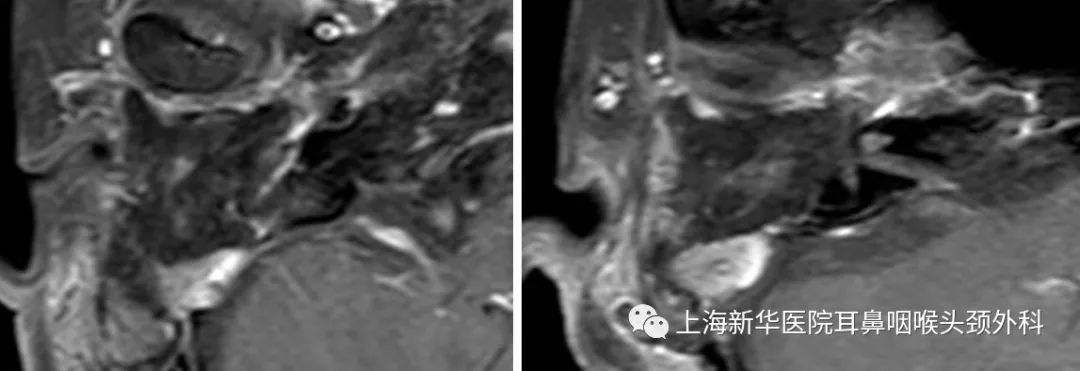

影像学检查:

术前MRI